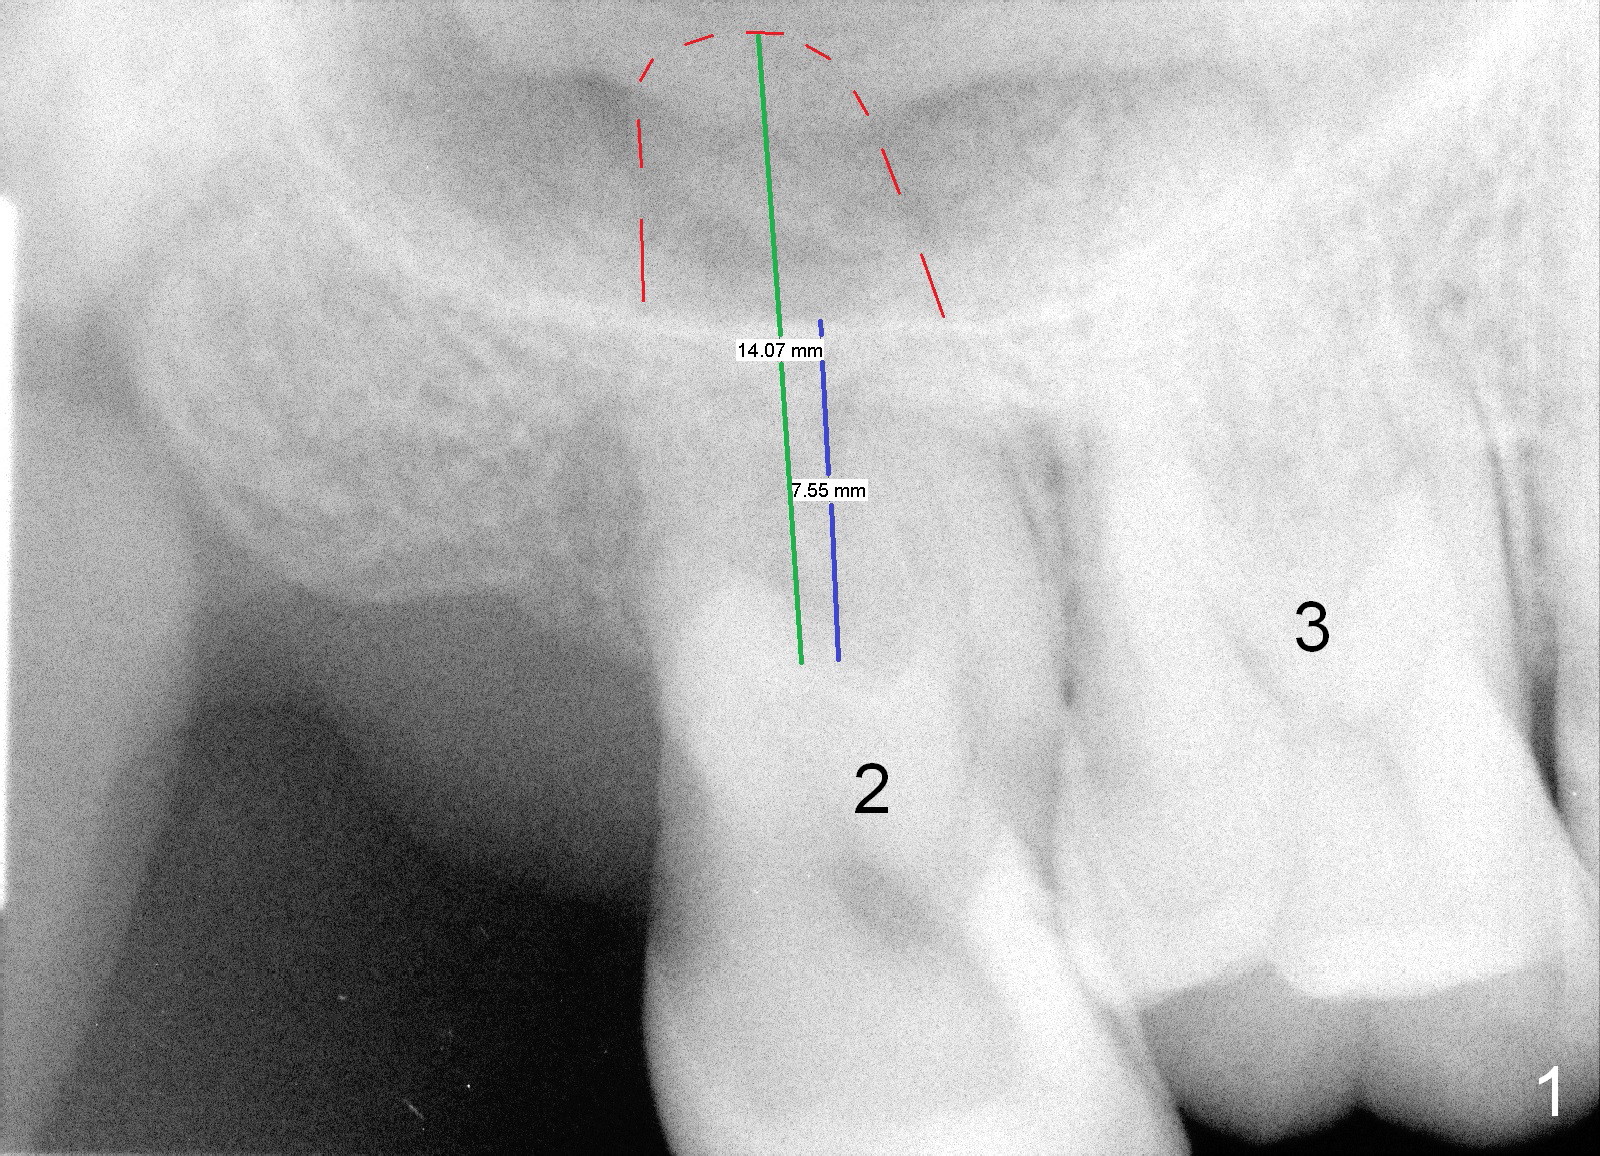

LJ will return for #2 implant placement 2 months post #31 implant placement. Fig.1 was taken 2 years ago. The tooth #2 had been supraerupted. The bone height is apparently 7.5 mm (blue line), but with proper manipulation, there would be 14 mm bone available (green line) for placement of an immediate implant. Fig.2 was taken a year post extraction. The bone height is reduced to 6 mm (blue line). With sinus lift, a 8 mm bone-level implant will be placed.